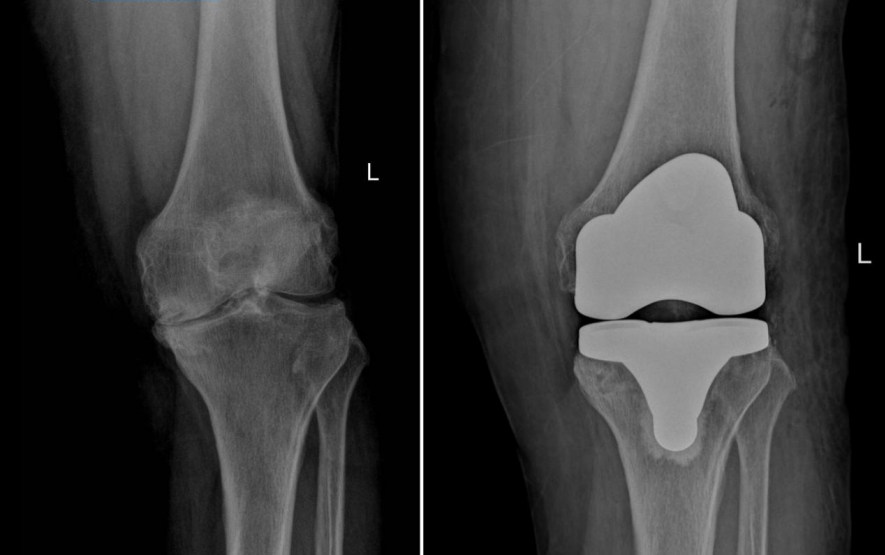

(▲右膝术前术后对比)

2022年10月,张阿姨在湖南省第二人民医院(省脑科医院)骨关节运动医学科诊断为双膝重度骨性关节炎,并接受右膝关节置换手术。出院后主治医生何改生积极微信与患者保持联系,指导康复训练,定期复查,右膝关节功能恢复良好,也不痛了。